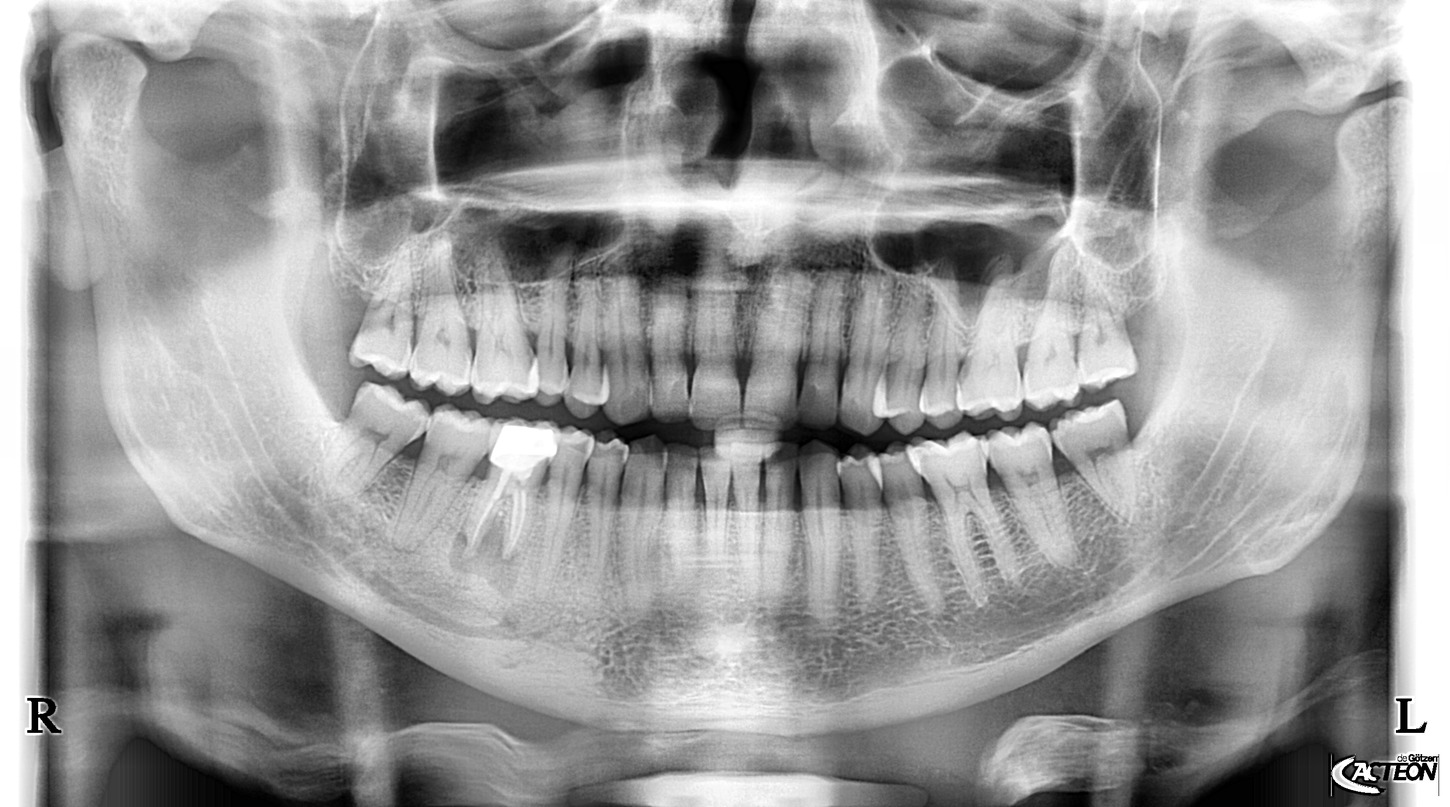

Panoramatické RTG s kefalo projekcí od výrobce Acteon (Satelec), jsou svými parametry a cenovou dostupností nejlepší volbou pro stomatologické praxe. Jedná se o OPG s kefalo ramenem, která svou kvalitou a ovládáním předčí všechna očekávání a řadí se tak mezi nejpoužívanější OPG v ortodontických ordinacích ve světě i u nás. Společnost Fénix Dental dodává všechny přístroje s odborným zaškolením a to dle individuální potřeby každého uživatele. Díky Aies SW je zobrazení OPG snímků bezkonkurenční. Díky panoramatickému RTG od výrobce Acteon, získáte nejpřesnější diagnostickou hodnotu, která snese ta nejpřísnější měřítka. Společnost Fénix Dental je autorizovaný servis pro produkty Acteon. Získejte precizní, přesné a kvalitní OPG snímky, kontaktujte nás.